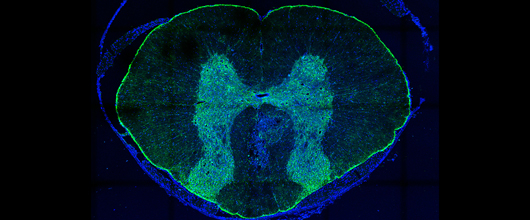

The ability to study astrocyte development in normal and pathological conditions, provides a unique opportunity to test the utility of glial precursor cells and their astrocytic progeny for cell transplantation therapy in diseases of the central nervous system (CNS), such as traumatic injury (spinal cord and traumatic brain injury) and neurodegenerative diseases (Parkinsons Disease, Multiple sclerosis).

We have identified distinct astrocyte populations that demonstrate different functional properties with respect to their ability to promote injury repair upon transplantation into the injured nervous system. While one type shows little benefit and may even cause neuropathic pain syndrome, the other remodels the injured host tissue, enables axon outgrowth and extensive functional recovery (J Biol 2006 Apr 27, 5(3):7; J Biol 2008 Sep 19;7(7):245). As a prerequisite for the transition to the clinic we are analyzing the factors secreted by these astrocytes and have now derived homologous astrocyte populations from human precursor cells. (PLoS One. 2011 Mar 2;6(3)).